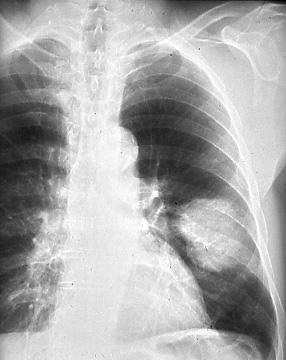

Fig. 9: T2, Atelectasis/pneumonitis extending to the hilar region. Posterior-anterior radiograph shows typical appearance of left upper lobe collapse with amputation of the left upper lobe bronchus, secondary to bronchogenic carcinoma, T2.